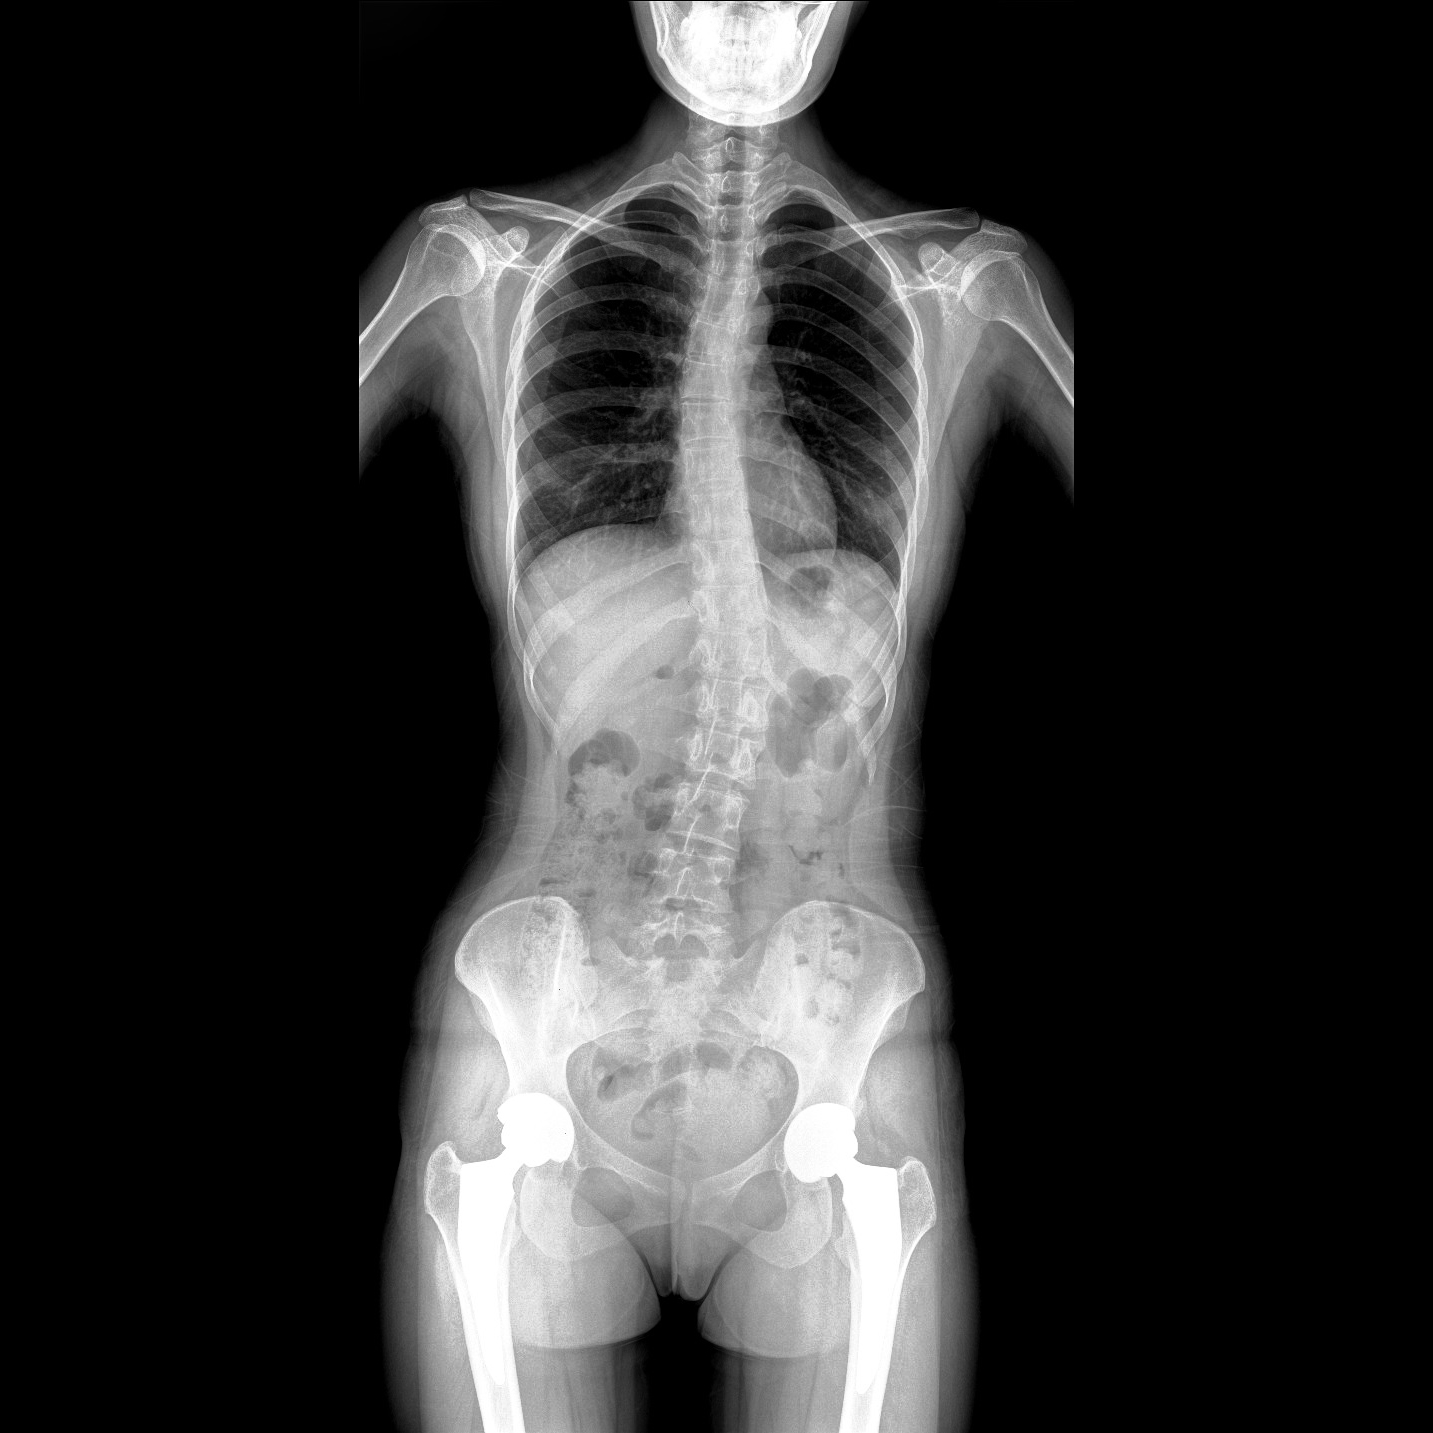

支持全脊柱摄影、双下肢摄影、脊髓造影、复杂创伤、人工关节置换、关节损伤的修复重建等大视野临床应用

全脊柱一次成像 不拼接

17"*34"有效视野,一次成像不拼接。相较于多张摄影再软件拼接的DR设备,PLX8600解决了拼接图像存在密度不均匀,拼接处图像配准和放大效应等问题,给临床带来了大视野影像解决方案,可一次性覆盖全脊柱或双下肢影像。

Clinical picture

临床图片